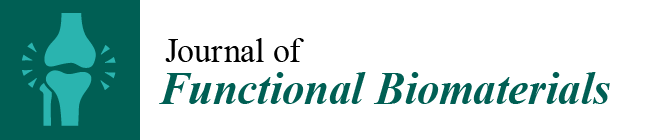

3.1. Rat

3.2. Rabbit

4. Large Animal Models

4.1. Sheep